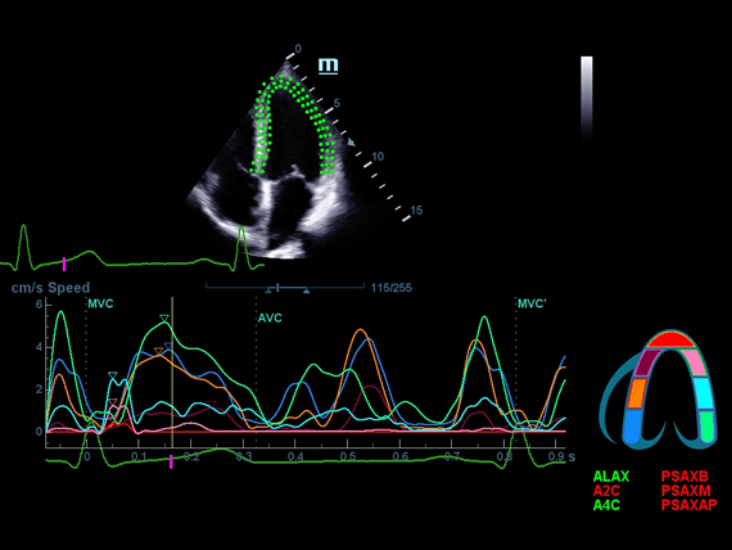

X-Insight is an insightful solution to envision more.

MindrayŌĆÖs brand-new solution is an excellent fusion of continuous customer insights into clinical needs, combined with continually evolving cutting-edge ultrasound technologies. Full of vitality, with the goal of insight into the future and pursuit of the infinity, it is constantly improving with increased scalability.

Based on the deep insights of customer needs, the DC-60 ECHO with X-Insight is designed to deliver high efficiency with precision imaging, which is empowered by eXpress Clarity, eXceptional Intelligence and eXceeding Experience.

eXceeding Experience

Experience with high productivity